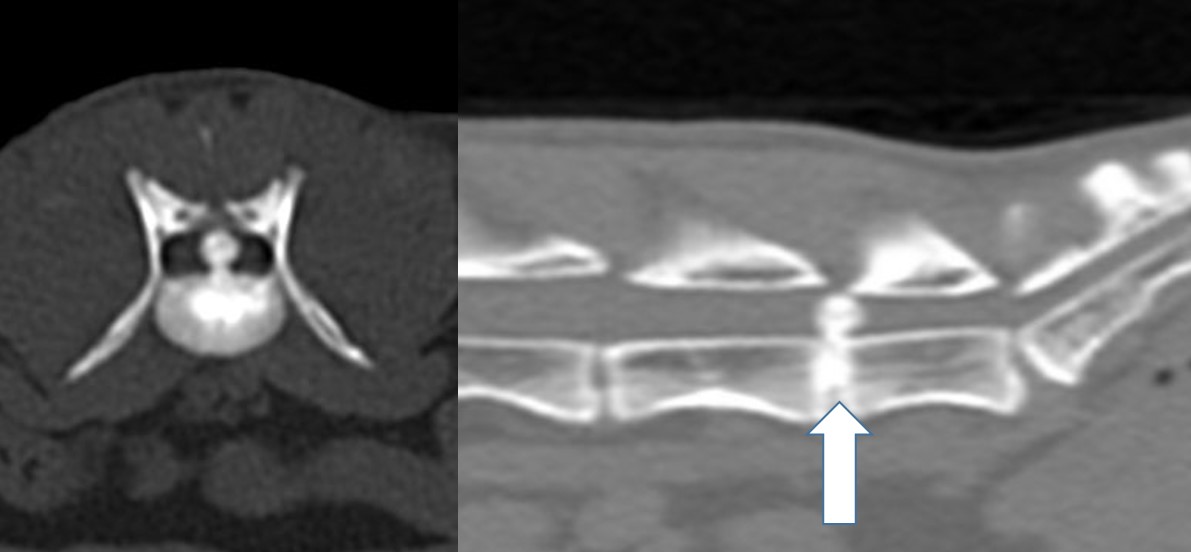

If your cat has a disk disease, which we finally diagnose with a CT or MRI, surgery has to be discussed if the hind legs are paralyzed. This is not so common, but we see patients like this from time to time (Fig 5).

Fig 5: Disk extrusion in a middle aged Siamese Cat

Fig 5: Disk extrusion in a middle aged Siamese Cat